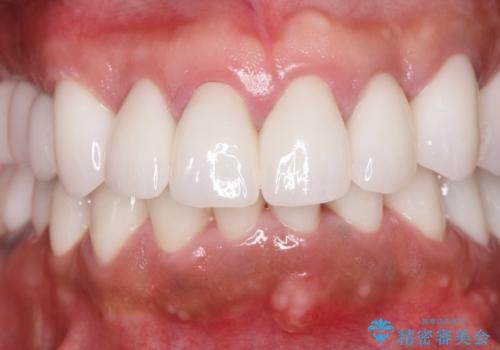

- 前医で行った前歯セラミック形態の改善、常に腫れぼったく歯ブラシの際に出血のある前歯部の治療を希望され来院されました。

歯周外科を行い歯と歯槽骨・歯肉の関係を是正することで歯ぐきの状態を改善し、将来に亘り安定した歯周環境の維持を期待できるセラミック治療を実践します。

歯ぐきが腫れたままの状態だと、違和感が生じるとともに常に炎症が存在する環境となってしまうので非常に好ましくない口腔内環境です。